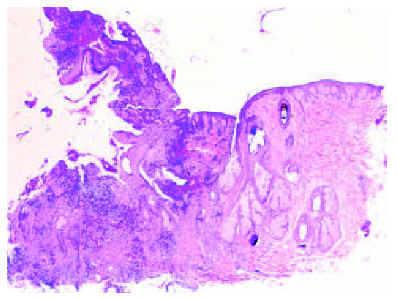

Un varón blanco sano de 16 años consultó por lesiones inflamatorias muy intensas en el cuero cabelludo de unos 4 meses de evolución, sin sintomatología sistémica asociada. En la exploración destacaban múltiples nódulos inflamatorios de 1 a 4 cm en el vértex y la región posterior del cuero cabelludo, con abundante supuración y tractos de drenaje interconectados (figs. 1 y 2). Presentaba además lesiones leves-moderadas de acné vulgar en cara y espalda. El estudio histopatológico mostró una foliculitis profunda aguda y crónica, con dilatación quística infundibular y reacción granulomatosa a cuerpo extraño (fig. 2). En el cultivo del aspirado se aisló flora mucocutánea grampositiva. La bioquímica general y el hemograma fueron normales. Ante la falta de respuesta a la doxiciclina y la rifampicina, iniciamos tratamiento oral con ácido 13-cis-retinoico (0,5 mg/kg/día) que fue efectivo; tras 7 meses sólo se apreciaban pequeñas lesiones residuales alopécicas (fig. 3). Se asoció prednisona oral (0,4 mg/kg/día) durante los primeros 2 meses de tratamiento.

Fig. 2.--Foliculitis profunda y seudofoliculitis con dilatación quística infundibular. (Hematoxilina-eosina, x20.)